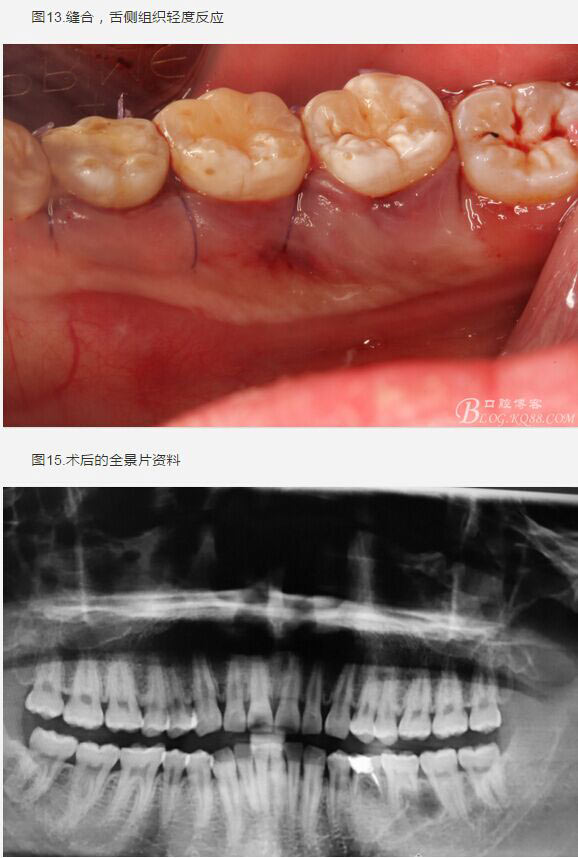

患者、盧xx、男、19歲。主訴:左側下頜乳磨牙未脫落,要求檢查。??茩z查:左側下頜第二乳磨牙有充填物。無松動,全景片檢查。35移位至36、37之間。頰舌側均不能觸及隆起。CBCT檢查:35位于36、37的舌側。表面骨質約2mm左右。35完全骨埋伏,36的遠中牙根疑是吸收。建議35暫觀察。置留不取。患者要求拔除擔心壓迫36牙根或者發(fā)生囊性變。術前簽手術同意書。